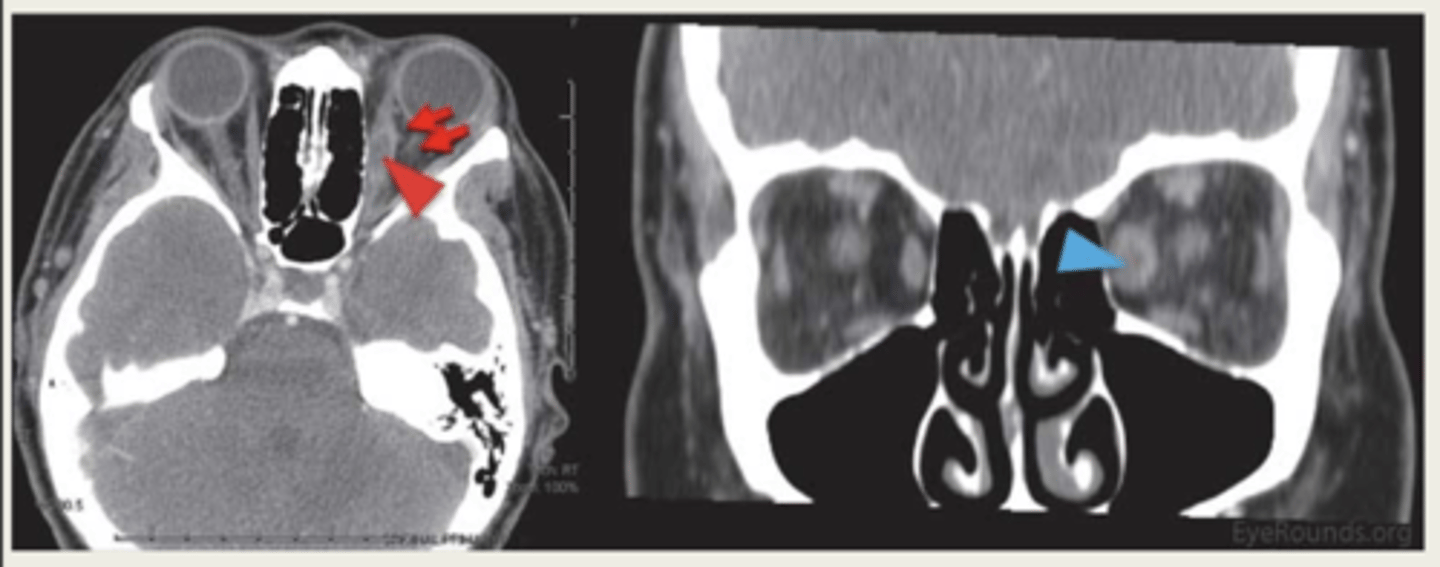

What is the workup for an orbital fracture?

CT scan

What causes an orbital fracture?

blunt trauma

What are the types of orbital fractures?

1. orbital floor (48%)

2. medial wall

force is displaced inferior and transmits energy from impact

What is the presentation of an orbital floor fracture?

1. lid bruising and edema

2. subcutaneous crepitus (crackling)

3. anesthesia of infraorbital nerve

4. limited IR & IO motility

5. bone step-off

6. proptosis

7. enophthalmos (if severe) - posterior displacement

What is the presentation of orbital medial wall fractures?

1. periorbital bruising

3. medial rectus entrapment, limited adduction

4. CSF rhinorrhea